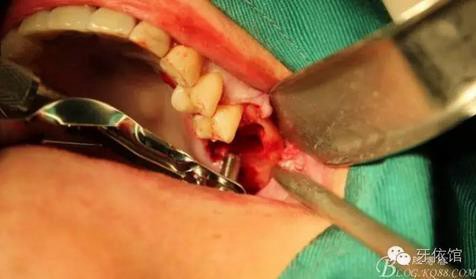

上6分根

依次拔除3個根

先在右上7的位置擴孔同時做內(nèi)提升

再在右上6牙根間隔擴孔、內(nèi)提

間隔上備的洞內(nèi)可以看到上頜竇膜

植入骨粉

植入植體

縫合